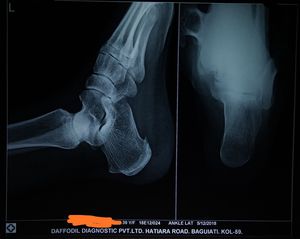

What is the diagnosis???

Calcaneum spur??